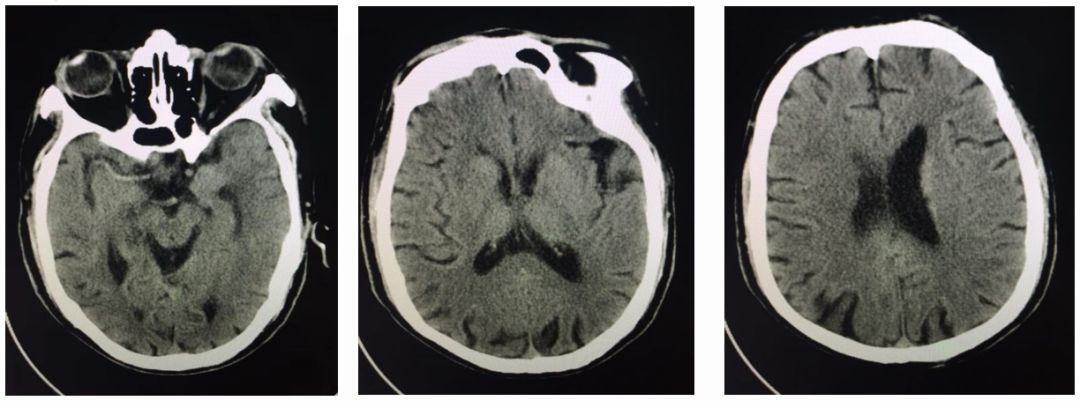

术后第3天,患者突然意识丧失,呼叫无反应,刺激右侧肢体无反应,左侧可见回缩,紧急头颅CT提示左侧半球大量脑出血并破入脑室,很快左侧瞳孔散大,深昏迷,家属拒绝行开颅血肿清除术,自动出院。

术后3天CT: